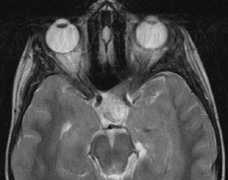

Optic pathway gliomas arise from the astrocytes of the optic nerve. Most are pilocytic astrocytomas and typically remain intradural, extending in the subdural space. Malignant transformation is rare. There appear to be two growth patterns62:

- Perineural growth pattern, correlating with a diagnosis of NF1. The tumor expands in the subarachnoid

space and the optic nerve is compressed as a central ribbon. On

T2-weighted MRI, this may be seen as a low-intensity core with surrounding

high-intensity rim. Increased tortuosity of the optic nerve is also

associated with this growth pattern (Fig. 5).63